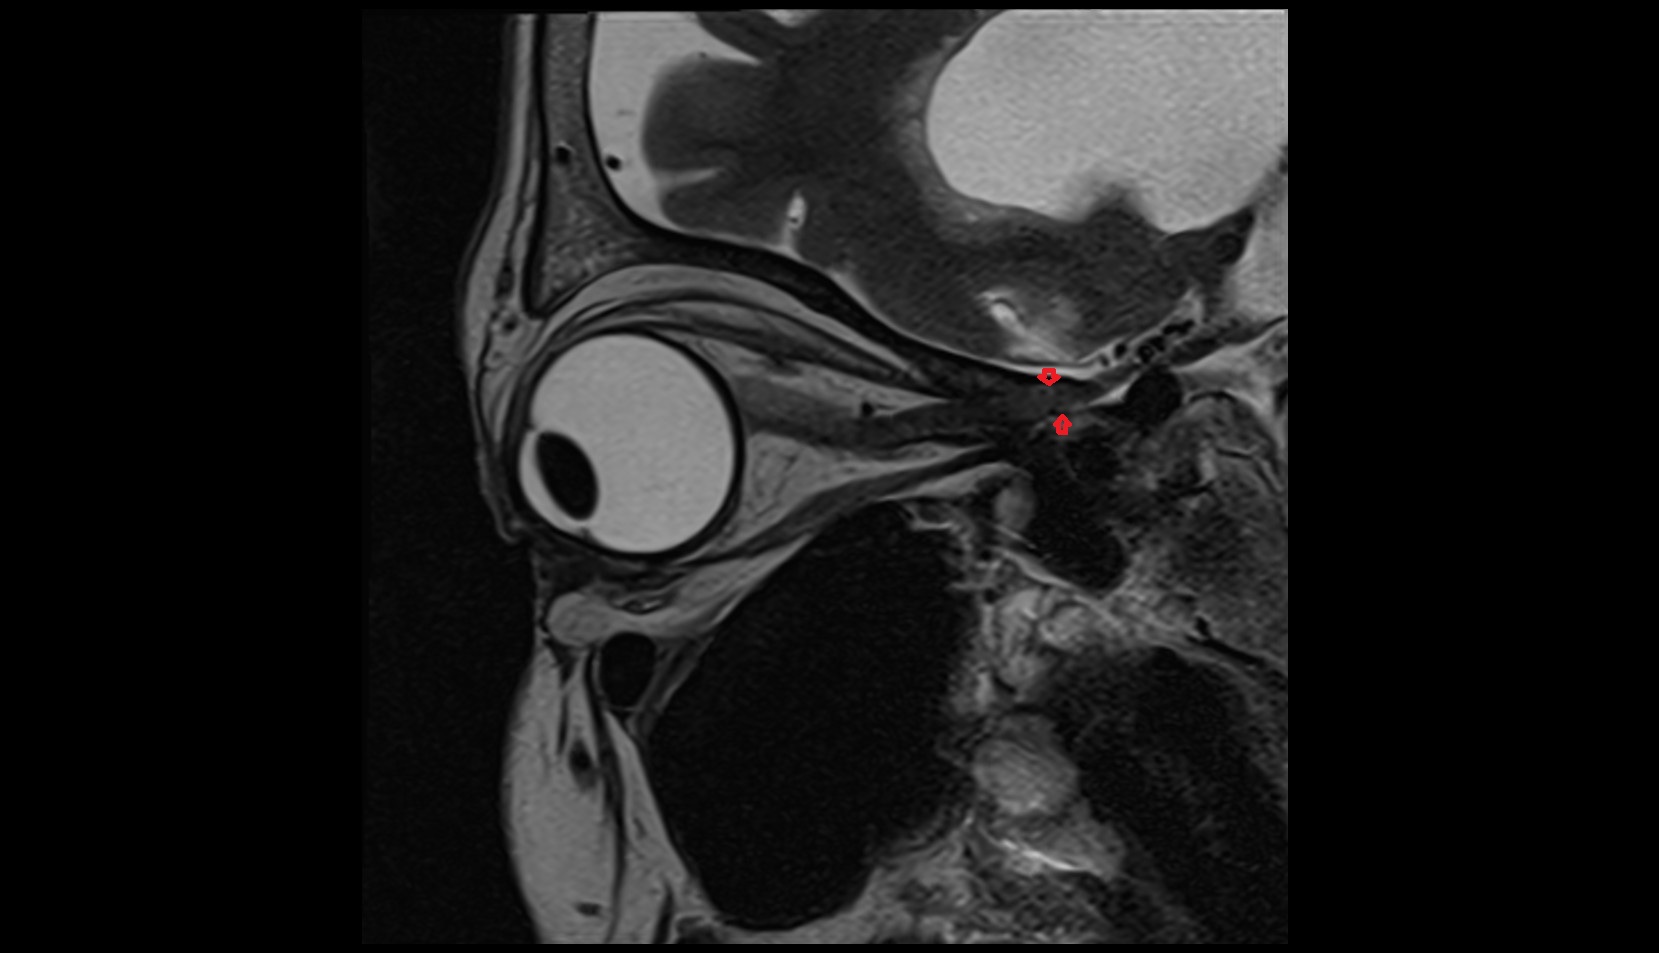

- Temporomandibular joint

- Articular disc of temporomandibular joint

- Articular eminence

- Mandibular condyle

- Mandibular fossa

- Superior head of lateral pterygoid muscle

- Inferior head of lateral pterygoid muscle